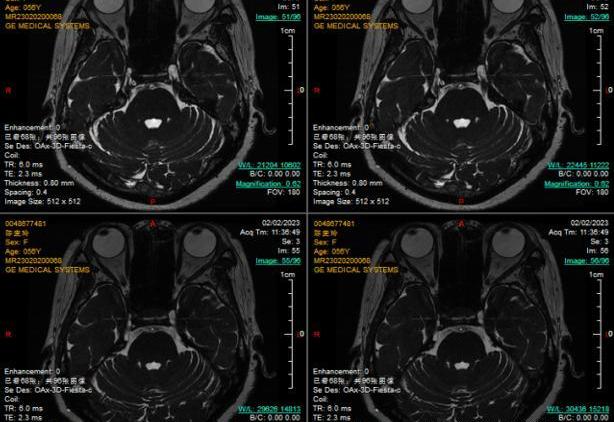

颅神经现象检查显示,胡先生右侧小脑上动脉分支骑跨左侧三叉神经,今年3月,西安交大一附院颅底颅神经疾病诊疗专家组姜海涛教授为他进行了显微血管减压手术治疗,术后面部疼痛消失,吃饭、说话、洗脸丝毫不受影响。

姜海涛教授:显微血管减压手术与传统的开颅手术不同,属于微创手术。手术在患侧耳后发际线内切开4cm左右的切口,颅骨钻开一元钱硬币大小的孔,医生在显微镜辅助下仔细探查三叉神经根部,找到压迫神经的“责任血管”,将其推移开来,用teflone垫片垫在中间,将其分离,只有这样血管对三叉神经的压迫才能消失,疼痛才能消失。